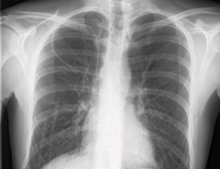

During subclavian vein central line placement, the catheter can be accidentally pushed into the internal jugular vein on the same side instead of the superior vena cava. A chest x-ray is performed after insertion to rule out this possibility.[18] The tip of the catheter can also be misdirected into the contralateral (opposite side) subclavian vein in the neck, rather than into the superior vena cava.

The line is then inserted using the Seldinger technique: a blunt guidewire is passed through the needle, then the needle is removed. A dilating device may be passed over the guidewire to expand the tract. Finally, the central line itself is then passed over the guidewire, which is then removed. All the lumens of the line are aspirated (to ensure that they are all positioned inside the vein) and flushed with either saline or heparin.[1] A chest X-ray may be performed afterwards to confirm that the line is positioned inside the superior vena cava and no pneumothorax was caused inadvertently; electromagnetic tracking can be used to verify tip placement and provide guidance during insertion, obviating the need for the X-ray afterwards.